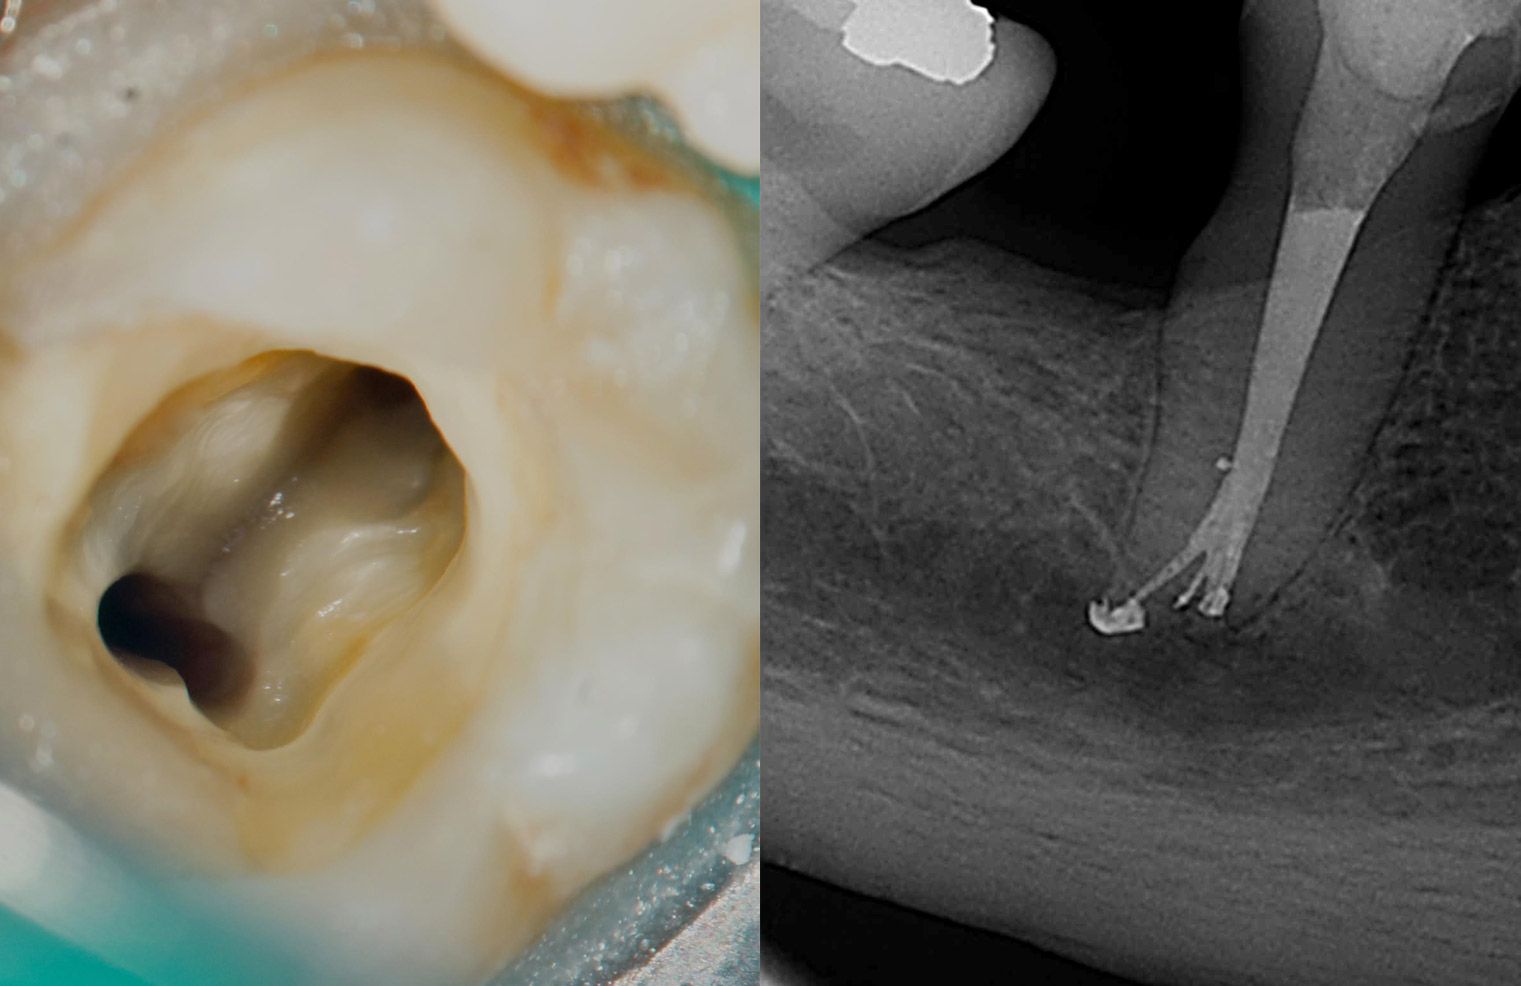

En la actualidad, la disciplina de Endodoncia se encarga de estudiar la morfología, fisiología, patología, diagnóstico y terapia del pulpo dentinario, fundamentándose en una evidencia científica que permanentemente se renueva, respaldada por las ciencias básicas y aplicando tecnologías clínicas de última generación.

El Programa para obtener el título profesional de Especialista en Endodoncia que dicta la Facultad de Odontología de la Universidad Finis Terrae otorga, mediante nuevos conocimientos teóricos y prácticos fundamentados en la evidencia científica, el uso de tecnología avanzada y la guía docente, las competencias necesarias para prevenir, diagnosticar y tratar las enfermedades inflamatorias de origen endodóntico de la más alta complejidad, promoviendo las relaciones interdisciplinares dentro de un marco ético y la formación continua de un especialista integral de primer nivel, en sintonía con las necesidades de salud bucal de la población.

• Los estudiantes tienen la oportunidad de llevar a cabo tratamientos endodónticos avanzados con el apoyo de microscopía en clínica, lo que les permite acceder a una práctica de alta especialización, mejorando la precisión y calidad en el diagnóstico y tratamiento de enfermedades endodónticas.

• El programa ofrece el uso de equipos y tecnología de última generación, brindando a los estudiantes las herramientas necesarias para desarrollar competencias avanzadas y mantenerse a la vanguardia en la especialidad de la endodoncia, mejorando su desempeño profesional en situaciones reales.